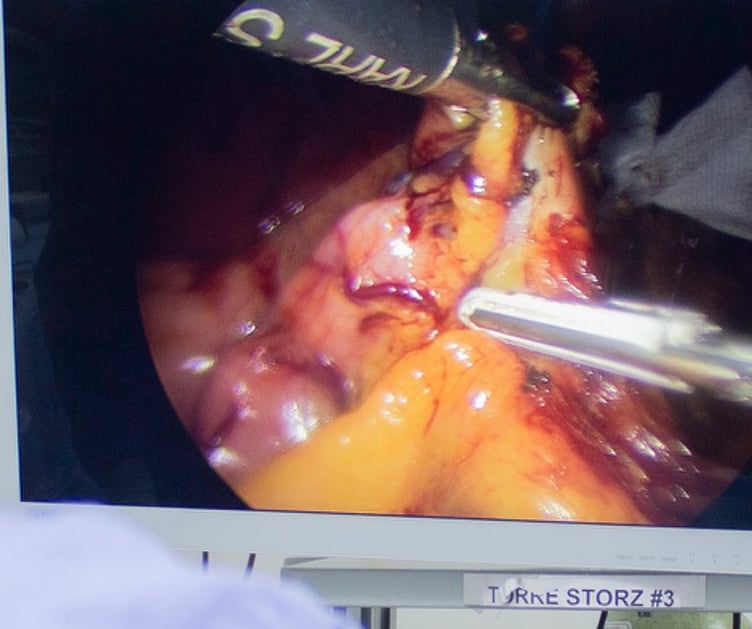

El bypass gástrico ofrece una pérdida de peso significativa y sostenida a largo plazo, además resolucion completa de comorbilidades como la diabetes o la hipertensión. Al reducir el tamaño del estómago y alterar la ruta del sistema digestivo, se limita la ingesta de alimentos y se disminuye la absorcion de los mismos.

El bypass gástrico brinda una esperanza renovada para aquellos que luchan con la obesidad y sus efectos secundarios devastadores. Además de la pérdida de peso, este procedimiento quirúrgico ha demostrado reducir el riesgo de complicaciones graves de salud, como accidentes cerebrovasculares y enfermedades cardíacas.

La preparación para la cirugía de bypass gástrico implica una evaluación exhaustiva del paciente, que incluye pruebas médicas, evaluación psicológica y cambios en el estilo de vida, como modificaciones en la dieta y el ejercicio físico. Antes de la cirugía, los pacientes deben seguir una dieta específica para reducir el tamaño del hígado y disminuir el riesgo de complicaciones durante la operación.